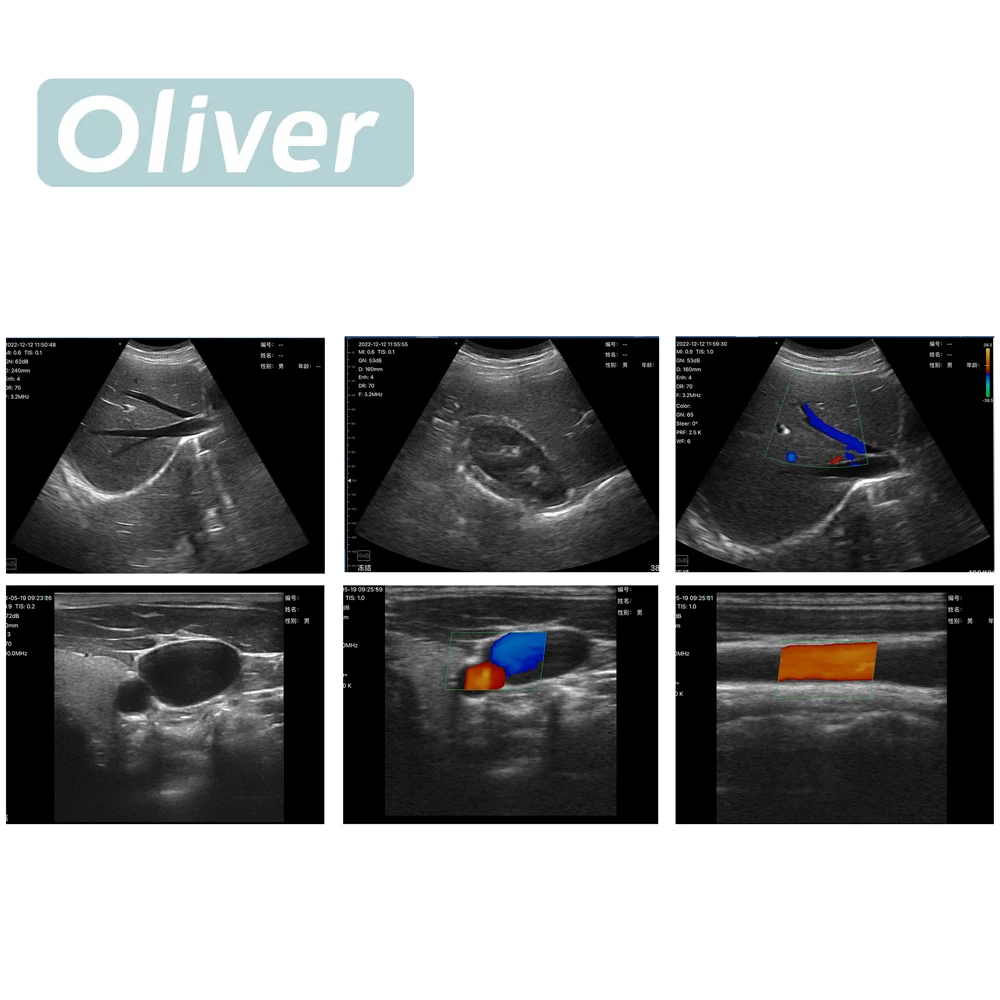

Sonda de ultrasonido inalámbrica de 256 elementos y 64 canales, escáner portátil con Wi-Fi, Doppler color, lineal y convexo 3 en 1

• Modo de escaneo: Matriz electrónica, matriz convexa electrónica y matriz lineal

• Frecuencia: Sonda convexa/de fase 3,2/5,0 MHz, sonda lineal 7,5/10 MHz

• Modos de visualización: B, B/M, Color, PDI, PW